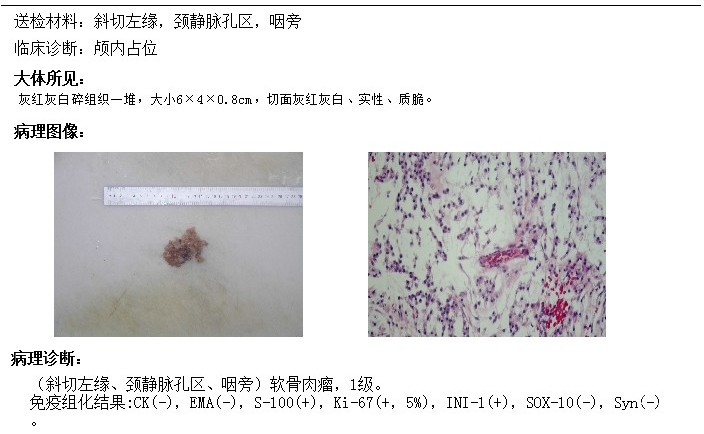

术前影像

术后影像

术后MRI提示肿瘤切除满意